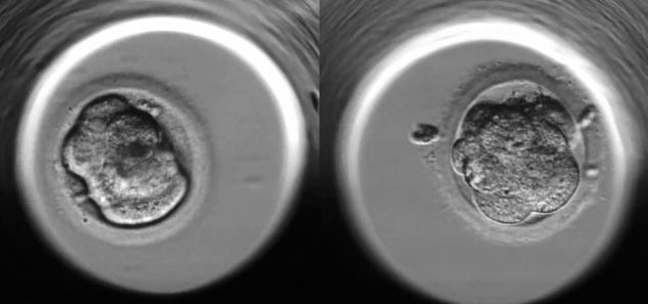

1η ώρα: Πριν τα ωάρια τοποθετηθούν στο «Εμβρυοσκόπιο» τοποθετούνται σε ένα υγρό που τους παρέχει συστατικά απαραίτητα για την ανάπτυξή τους.

12η ώρα: Ένα επιτυχώς γονιμοποιημένο ωάριο περιέχει δύο «σφαίρες», μία από το ωάριο και μία από το σπερματοζωάριο. Μέσα τους εμπεριέχεται το γενετικό υλικό της νέας ζωής.

24η ώρα: Ένα ωάριο χωρίζεται σε δύο κύτταρα.

30η ώρα: Μεγάλη ανακούφιση για τους Fisher, η εξέλιξη των κυττάρων δείχνει πολύ καλές προοπτικές.